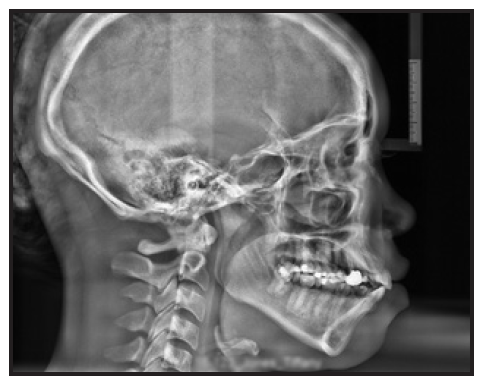

This is kinda doxxing and decomp doesnt work that way, he is class 3 and his teeth doesnt sit right on his bone if you look at the scans they are tilted from the nasal base and then to the lower jaw. But obv its not possible to tilt them so he actually can move maxilla without peoclined teeth so he will look like a ape post op. Thats also the reason why looking at this pics from below when the bone above is too short either way

Its like this(pic below), wow the front teeth is infront but obv the teeth is proclined so he looks like a ape. This dude also needs extractions, because there will be no room for to reverse the proclined teeth otherwise. And having this proclined teeth is not good for longevity either way